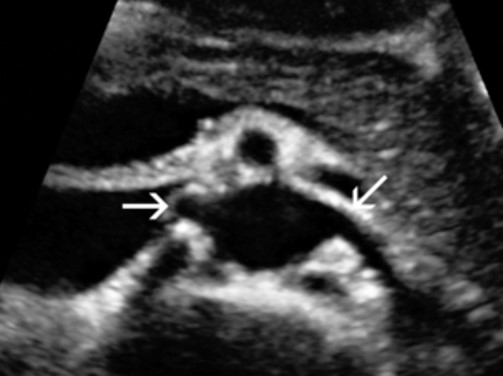

<p>In this Sagittal-Coronal plane, what is #1?</p>

In this Sagittal-Coronal plane, what is #1?

Right Renal Artery

<p>In this Sagittal-Coronal plane, what is #2?</p>

In this Sagittal-Coronal plane, what is #2?

Left Renal Artery

<p>In this Sagittal-Coronal plane, what is #3?</p>

In this Sagittal-Coronal plane, what is #3?

Aorta